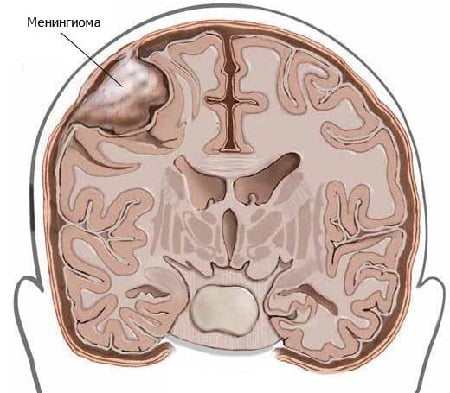

Менингиома — опухоль головного мозга, в основном она имеет доброкачественный характер. На долю менингиом приходится около 15% всех опухолей головного мозга. Эта опухоль состоит из арахноидальной оболочки головного мозга. Большая часть доброкачественных менингиом имеет медленный рост и достигает больших размеров, оставаясь незамеченной. Рост возможен в нескольких частях головного мозга.

Менингиома располагается вдоль основания черепа и оболочки венозных синусов. Очень часто она встречается в парасагиттальном синусе, затылочном отверстии, в области больших полушарий мозга и мостомозжечковом углу.

Наиболее часто внутричерепные менингиомы располагаются парасагиттально и на фальксе (25%). Конвекситально в 19% случаев. На крыльях основной кости — 17%. Супраселлярно — 9%. Задняя черепная ямка — 8%. Ольфакторная ямка — 8%. Средняя черепная ямка — 4%. Намет мозжечка — 3%. В боковых желудочках, большом затылочном отверстии и зрительном нерве по 2%.